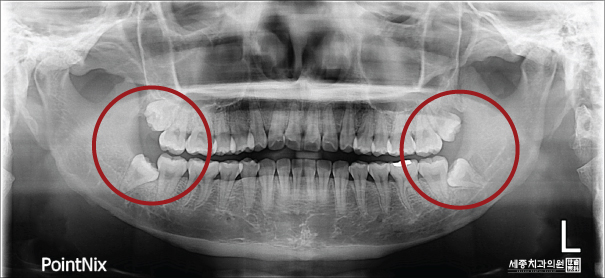

일단, 긴 말은 넣어두고 파노라마 사진으로 제 사랑니 발치 전 모습을 보여드리겠습니다.

C.T 촬영 후 저는 좌절했습니다.

사랑니 총 4개, 모두 발치를 해야 하는데 대학병원에서 발치 가능한 치아라고 진단이 내려졌기 때문입니다.

하지만 세종치과에서는 불가능한 발치란 없었습니다!!!

제일 불편한 왼쪽 위, 아래 사랑니 발치와 스케일링을 함께 진료받기로 했답니다~